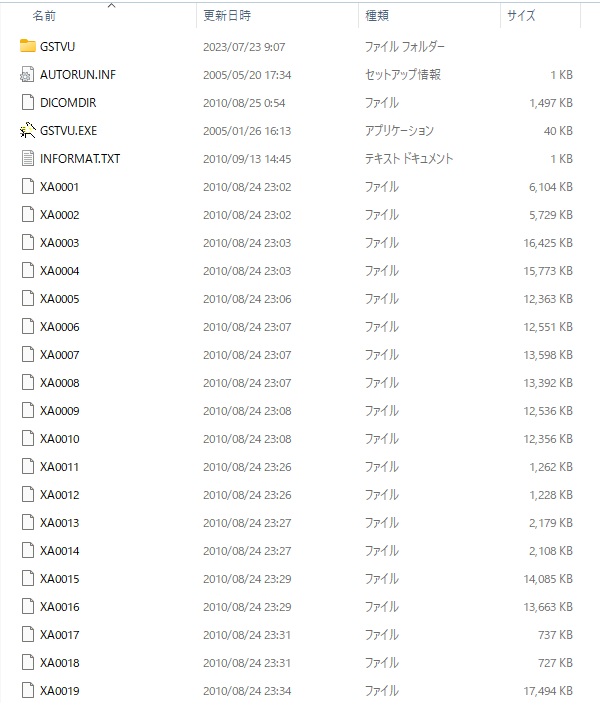

動画の記録は23時02分より開始(カテーテル手技開始から27分間のブランクあり)。カテーテル手技開始後、右橈骨動脈から冠動脈へのアプローチ失敗の動画が存在しない。大事故のため、抜き取られた可能性がある。

証拠:PCI動画の更新時間:最初の動画が23:02となっており、それ以前の27分間の動画が存在しない。

心カテ検査記録によると、PCIでの放射線被曝量は10350mGyに達し、許容量を大幅に超過。

証拠:PCIレポート